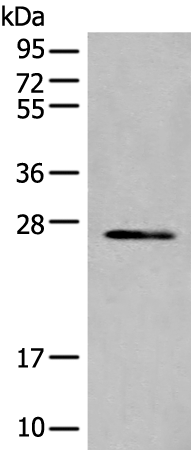

分类: 科研抗体货号: P02430别名:应用: WB,IHC反应种属: Human